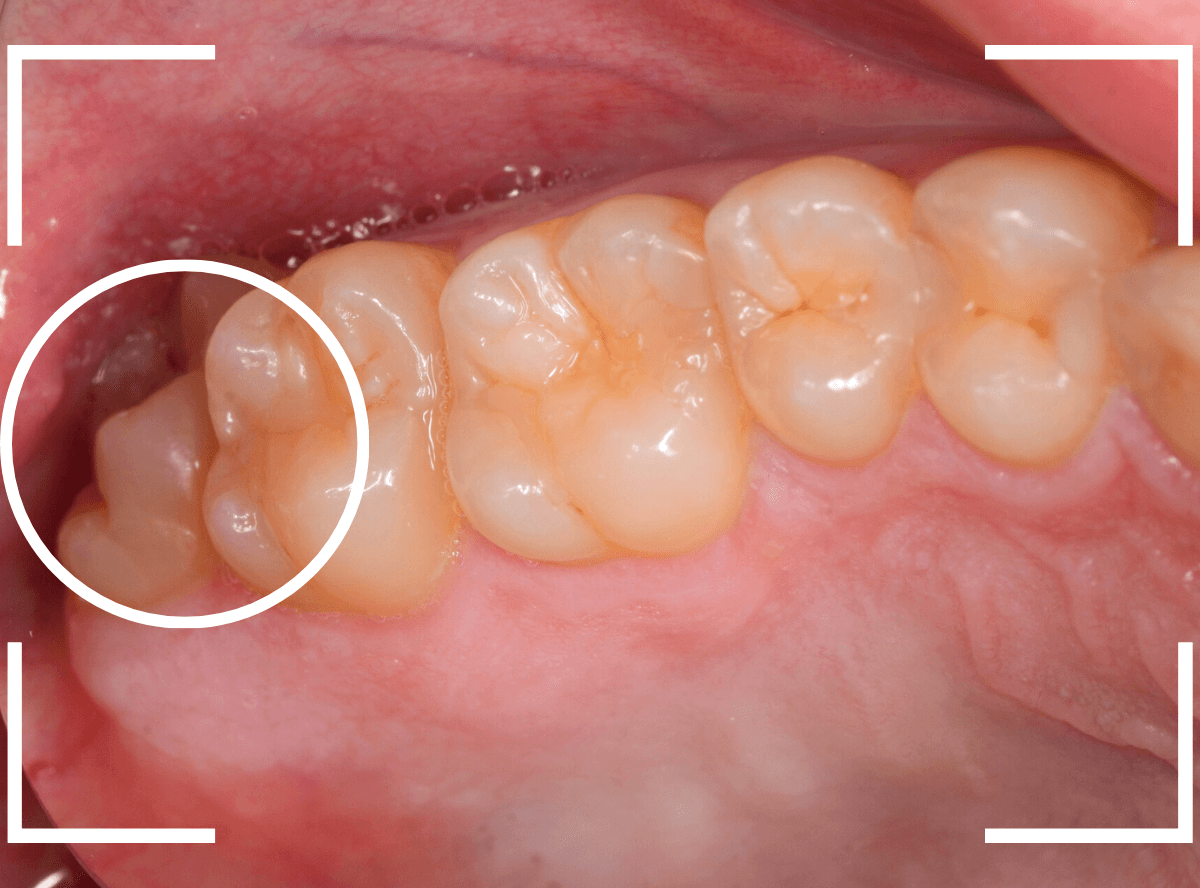

このようなおやしらず、あなたはありませんか?